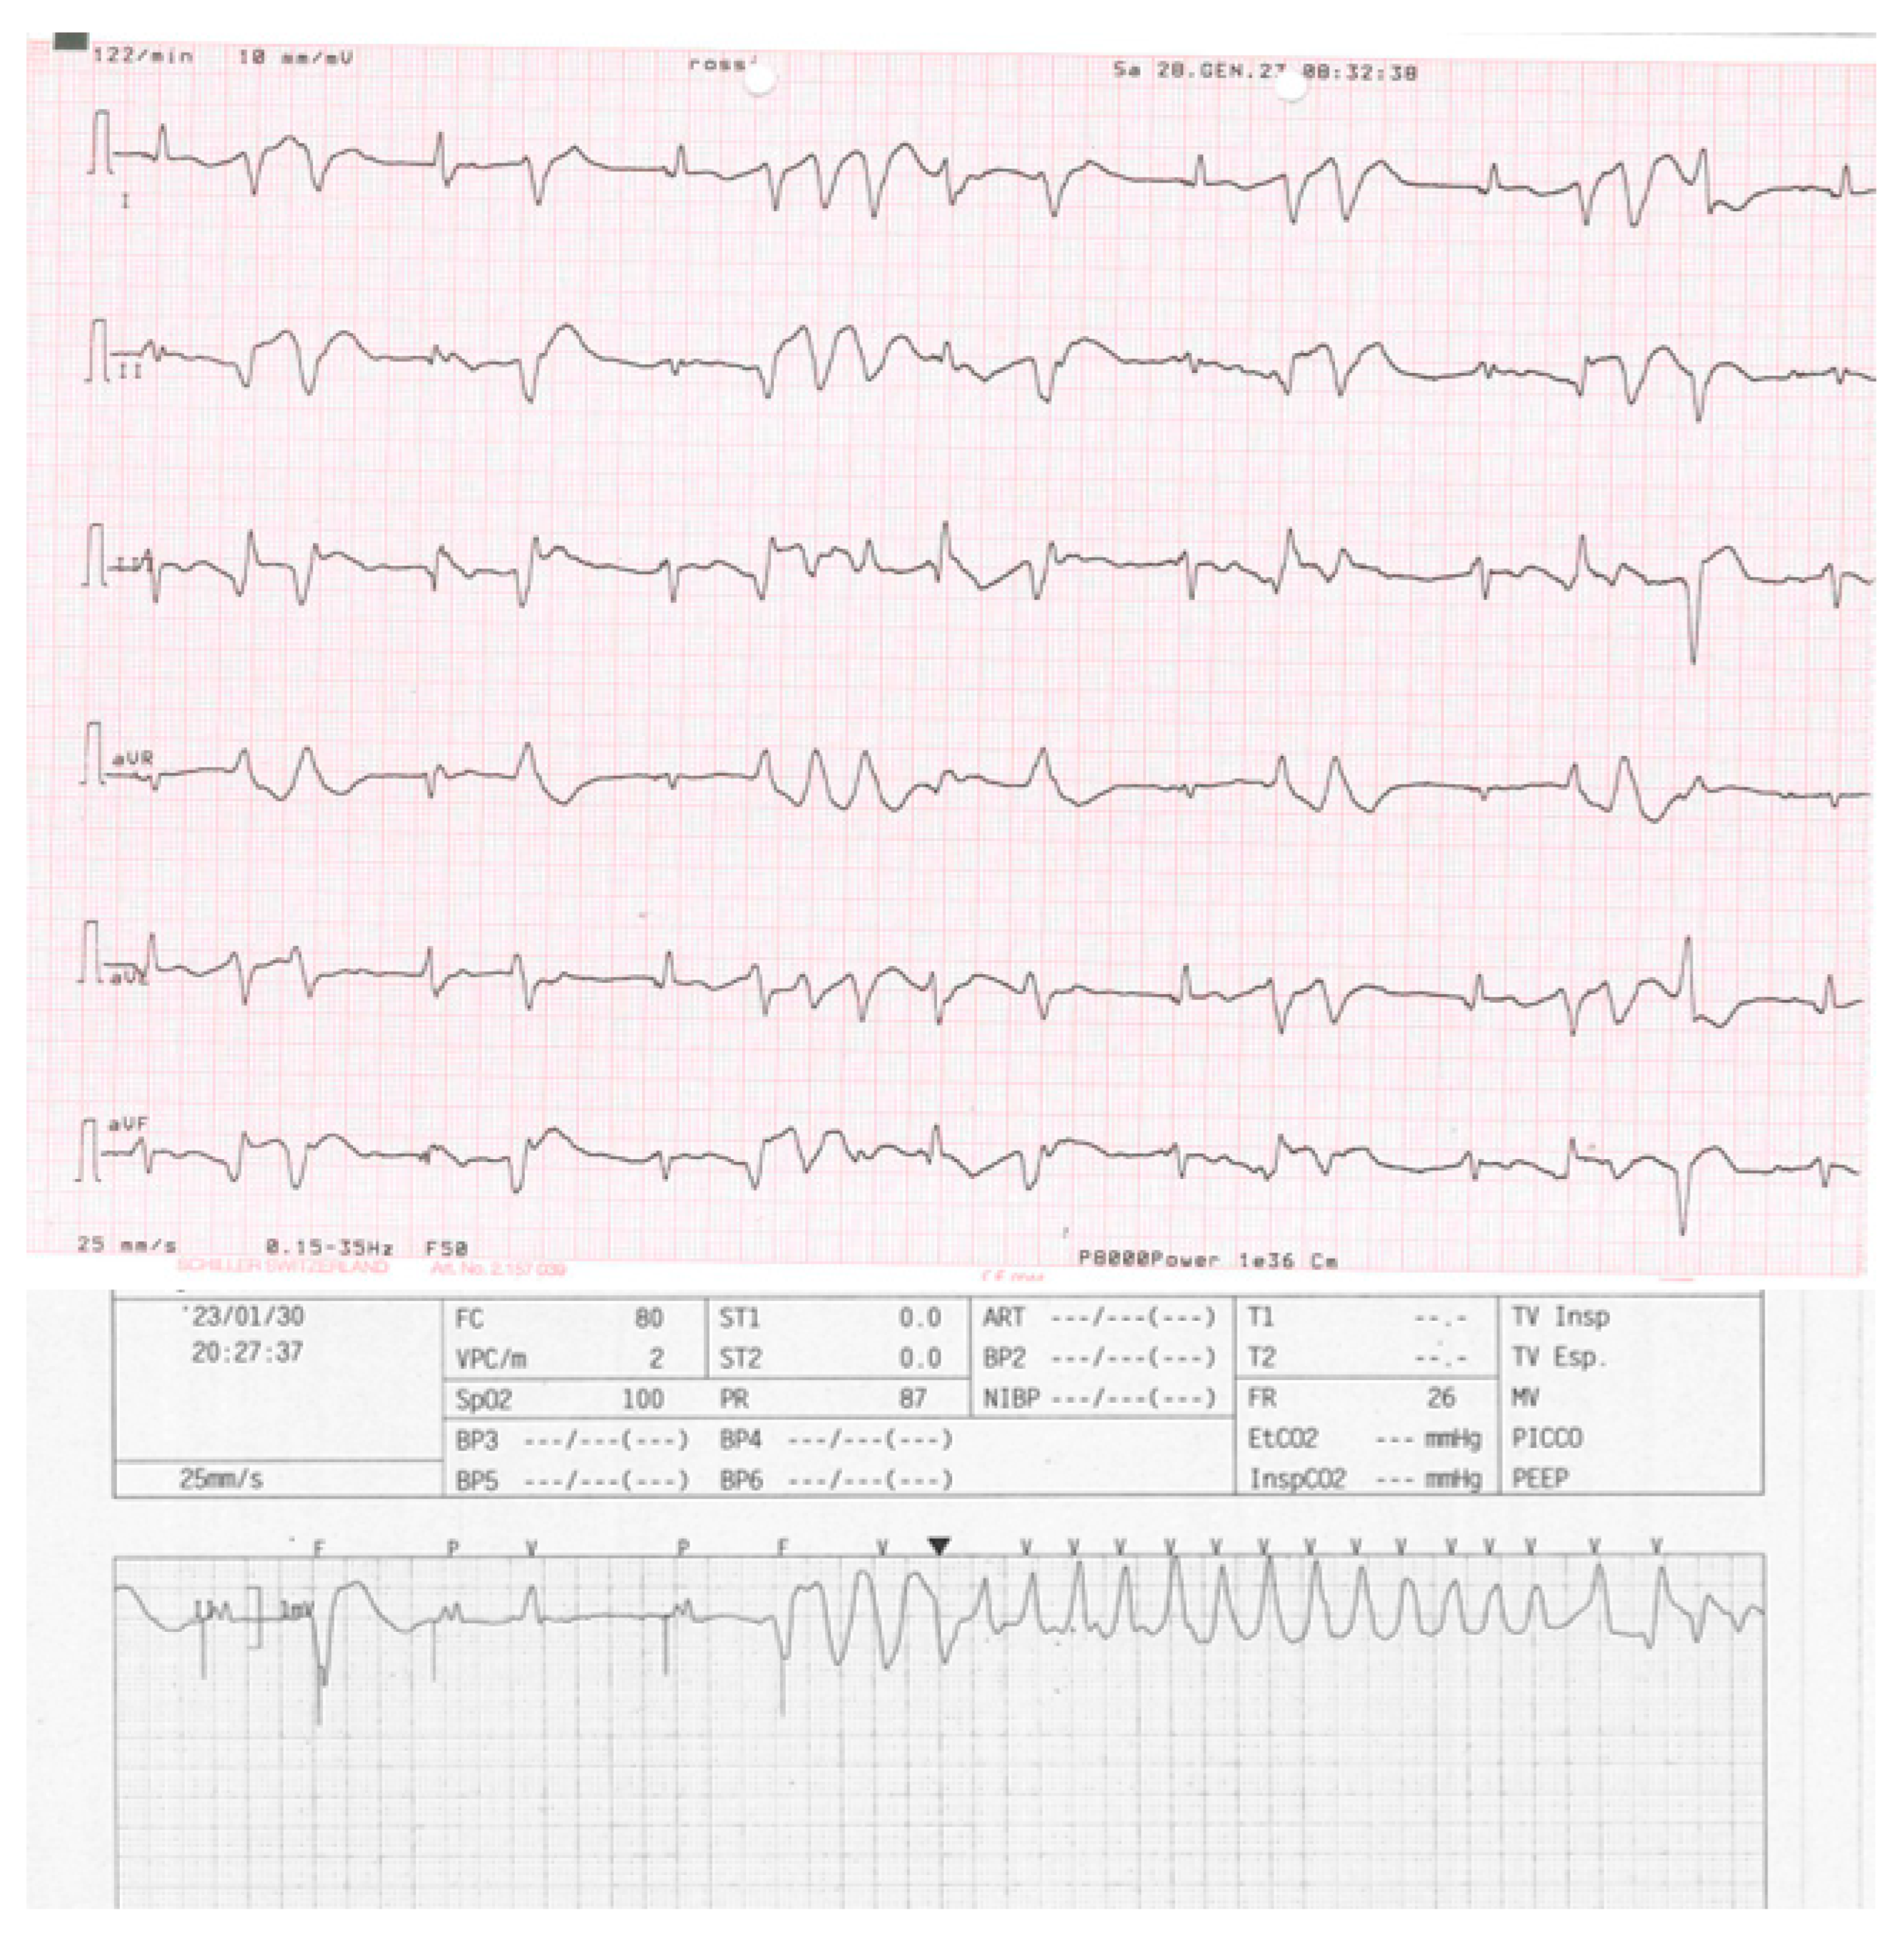

In 2022 after history of HF, hypocinetic cardiomyopathy with AF - not controlled frequency, an upgrade to CRTD implantation was programmed followed by the NAV ablation in order to reduce the elevated frequency of AF despite medical optimization (see Figure 1 for the correct position of electrocatheters after implantation). During the night, caused by an initial delirium , it has been initiated quetiapine and haloperidol in order to control the psychotic poussee. The day after the CRTD implantation, polymorphic ventricular tachycardia have been registered, initially treated with magnesium intravenously and an increment of bisoprolol dosage (see Figure 2 and Figure 3). According to the hypothesis of a proarrhythmic damage due to the new LV stimulation, a check of the device has been performed but the mechanism of CRT-induced proarrhythmia remains unknown during the LV stimulation (single site, D1-M1 configuration).

Figure 2. The polymorphic arrhythmic activity in the 6-leads electrocardiogram after 2 two-day after implantation. During the evening, telemetric single-lead registration of polymorphic nsVT.